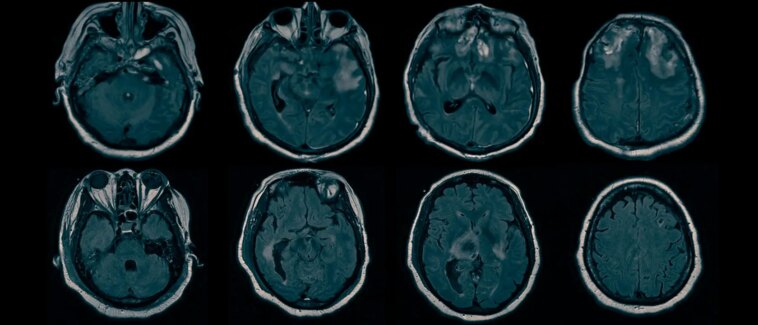

Les examens IRM révèlent des lésions cérébrales sous-jacentes à une conscience cachée. Crédit : Laboratoire Claassen, Centre médical Irving de l’Université Columbia

Les chercheurs ont ensuite analysé les IRM structurelles de tous les patients.

« En utilisant une technique que nous avons développée appelée analyse bi-clustering, nous avons pu identifier des modèles de lésions cérébrales communes aux patients atteints de DMC et contrastés avec ceux sans DMC », explique le co-auteur principal Qi Shen, PhD, chercheur associé à le laboratoire Claassen et expert en traitement du signal, apprentissage automatiqueet biostatistiques.